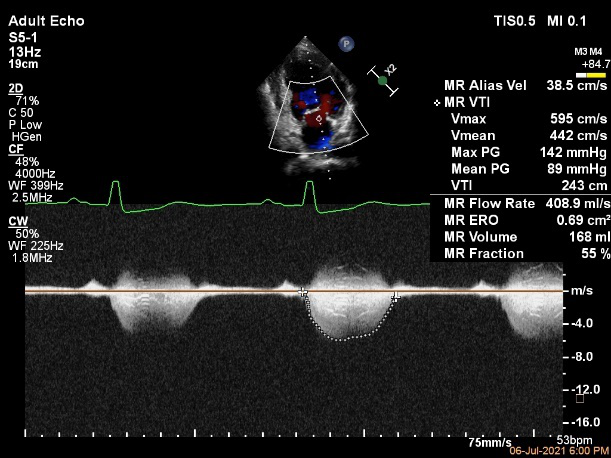

Bicom:MR(重度),返流束宽15.8mm,返流面积10.6cm²

PISA法定量EROA:0.69cm²,Rvol:168ml,RF:55%

肺静脉血流频谱呈收缩期反向

TEE Bicom返流量评估

TEE 4-Ch view返流量评估